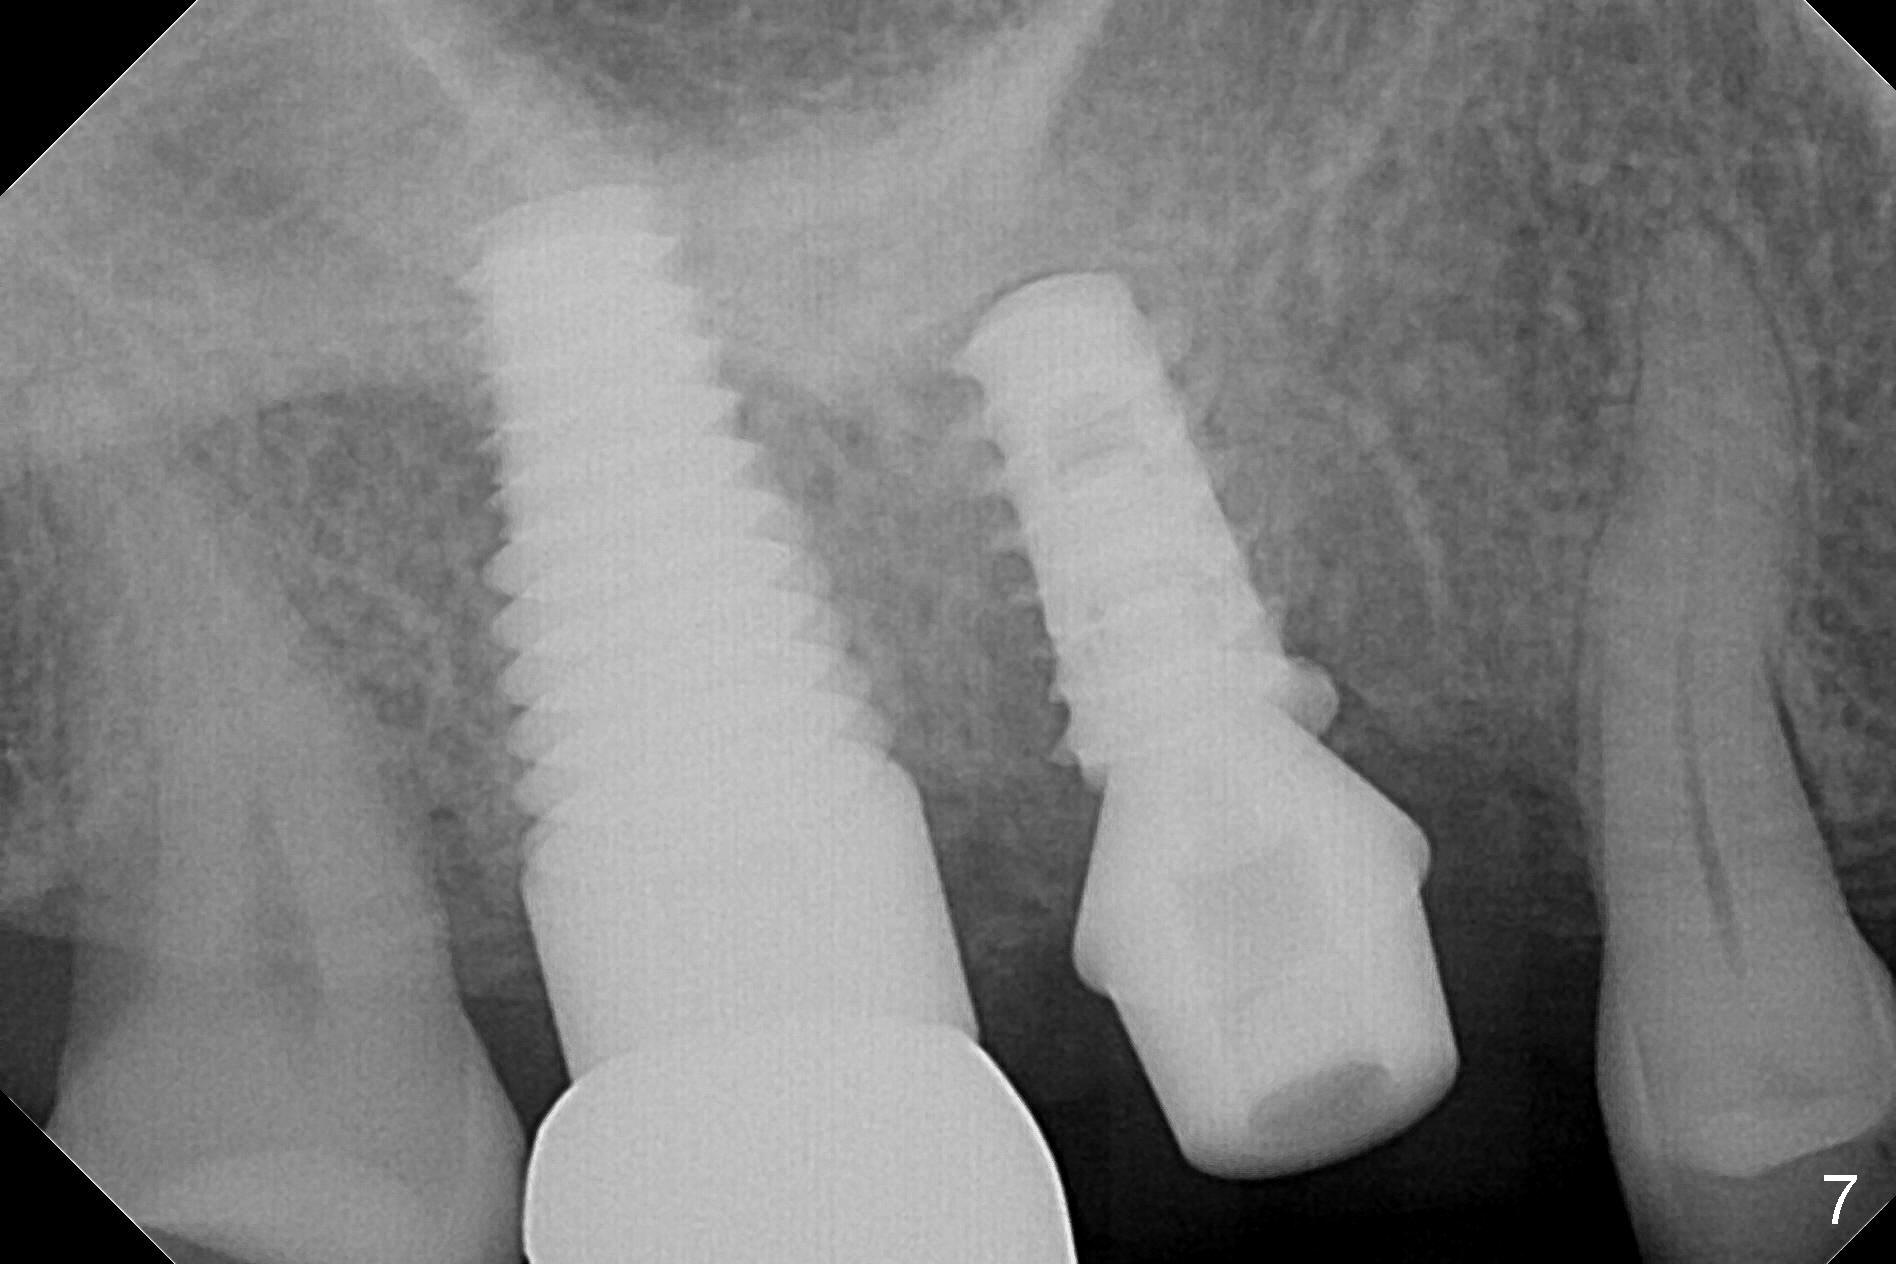

The patient returns with chief complaint of crown is loose with pain 3 months postop (Fig.7). Under local anesthesia, the provisional is removed. The gingiva is erythematous. The implant has mobility. A healing abutment is placed (6x2 mm). One month later, the implant remains unstable. The patient is scheduled to return 3.5 months postop to either retighten the implant with healing screw or replace with a 6x17 mm Tatum implant (Fig.9) after changing trajectory (Fig.8 red arrow).